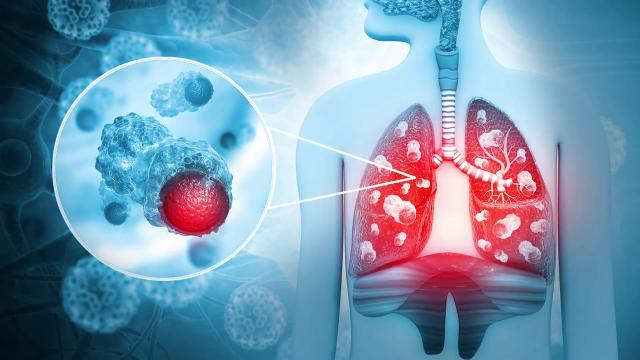

폐암의 초기에 나타나는 증상

세 번째로 주목해야 할 증상은 혈액이 섞인 가래입니다. 건강한 경우에는 가래에서 피가 나오는 일이 드물지만, 폐암 환자의 경우 고형 종양으로 인해 혈액이 혼합되는 경우가 있습니다. 이 증상을 간과해서는 안 됩니다.

가장 일반적으로 시행되는 검사는 흉부 X선 촬영과 CT 스캔입니다. 이러한 검사를 통해 폐에 이상 징후가 있는지를 확인할 수 있습니다. 초기 증상이 나타나는 경우 때에 따라 추가 검사가 필요할 수도 있습니다.